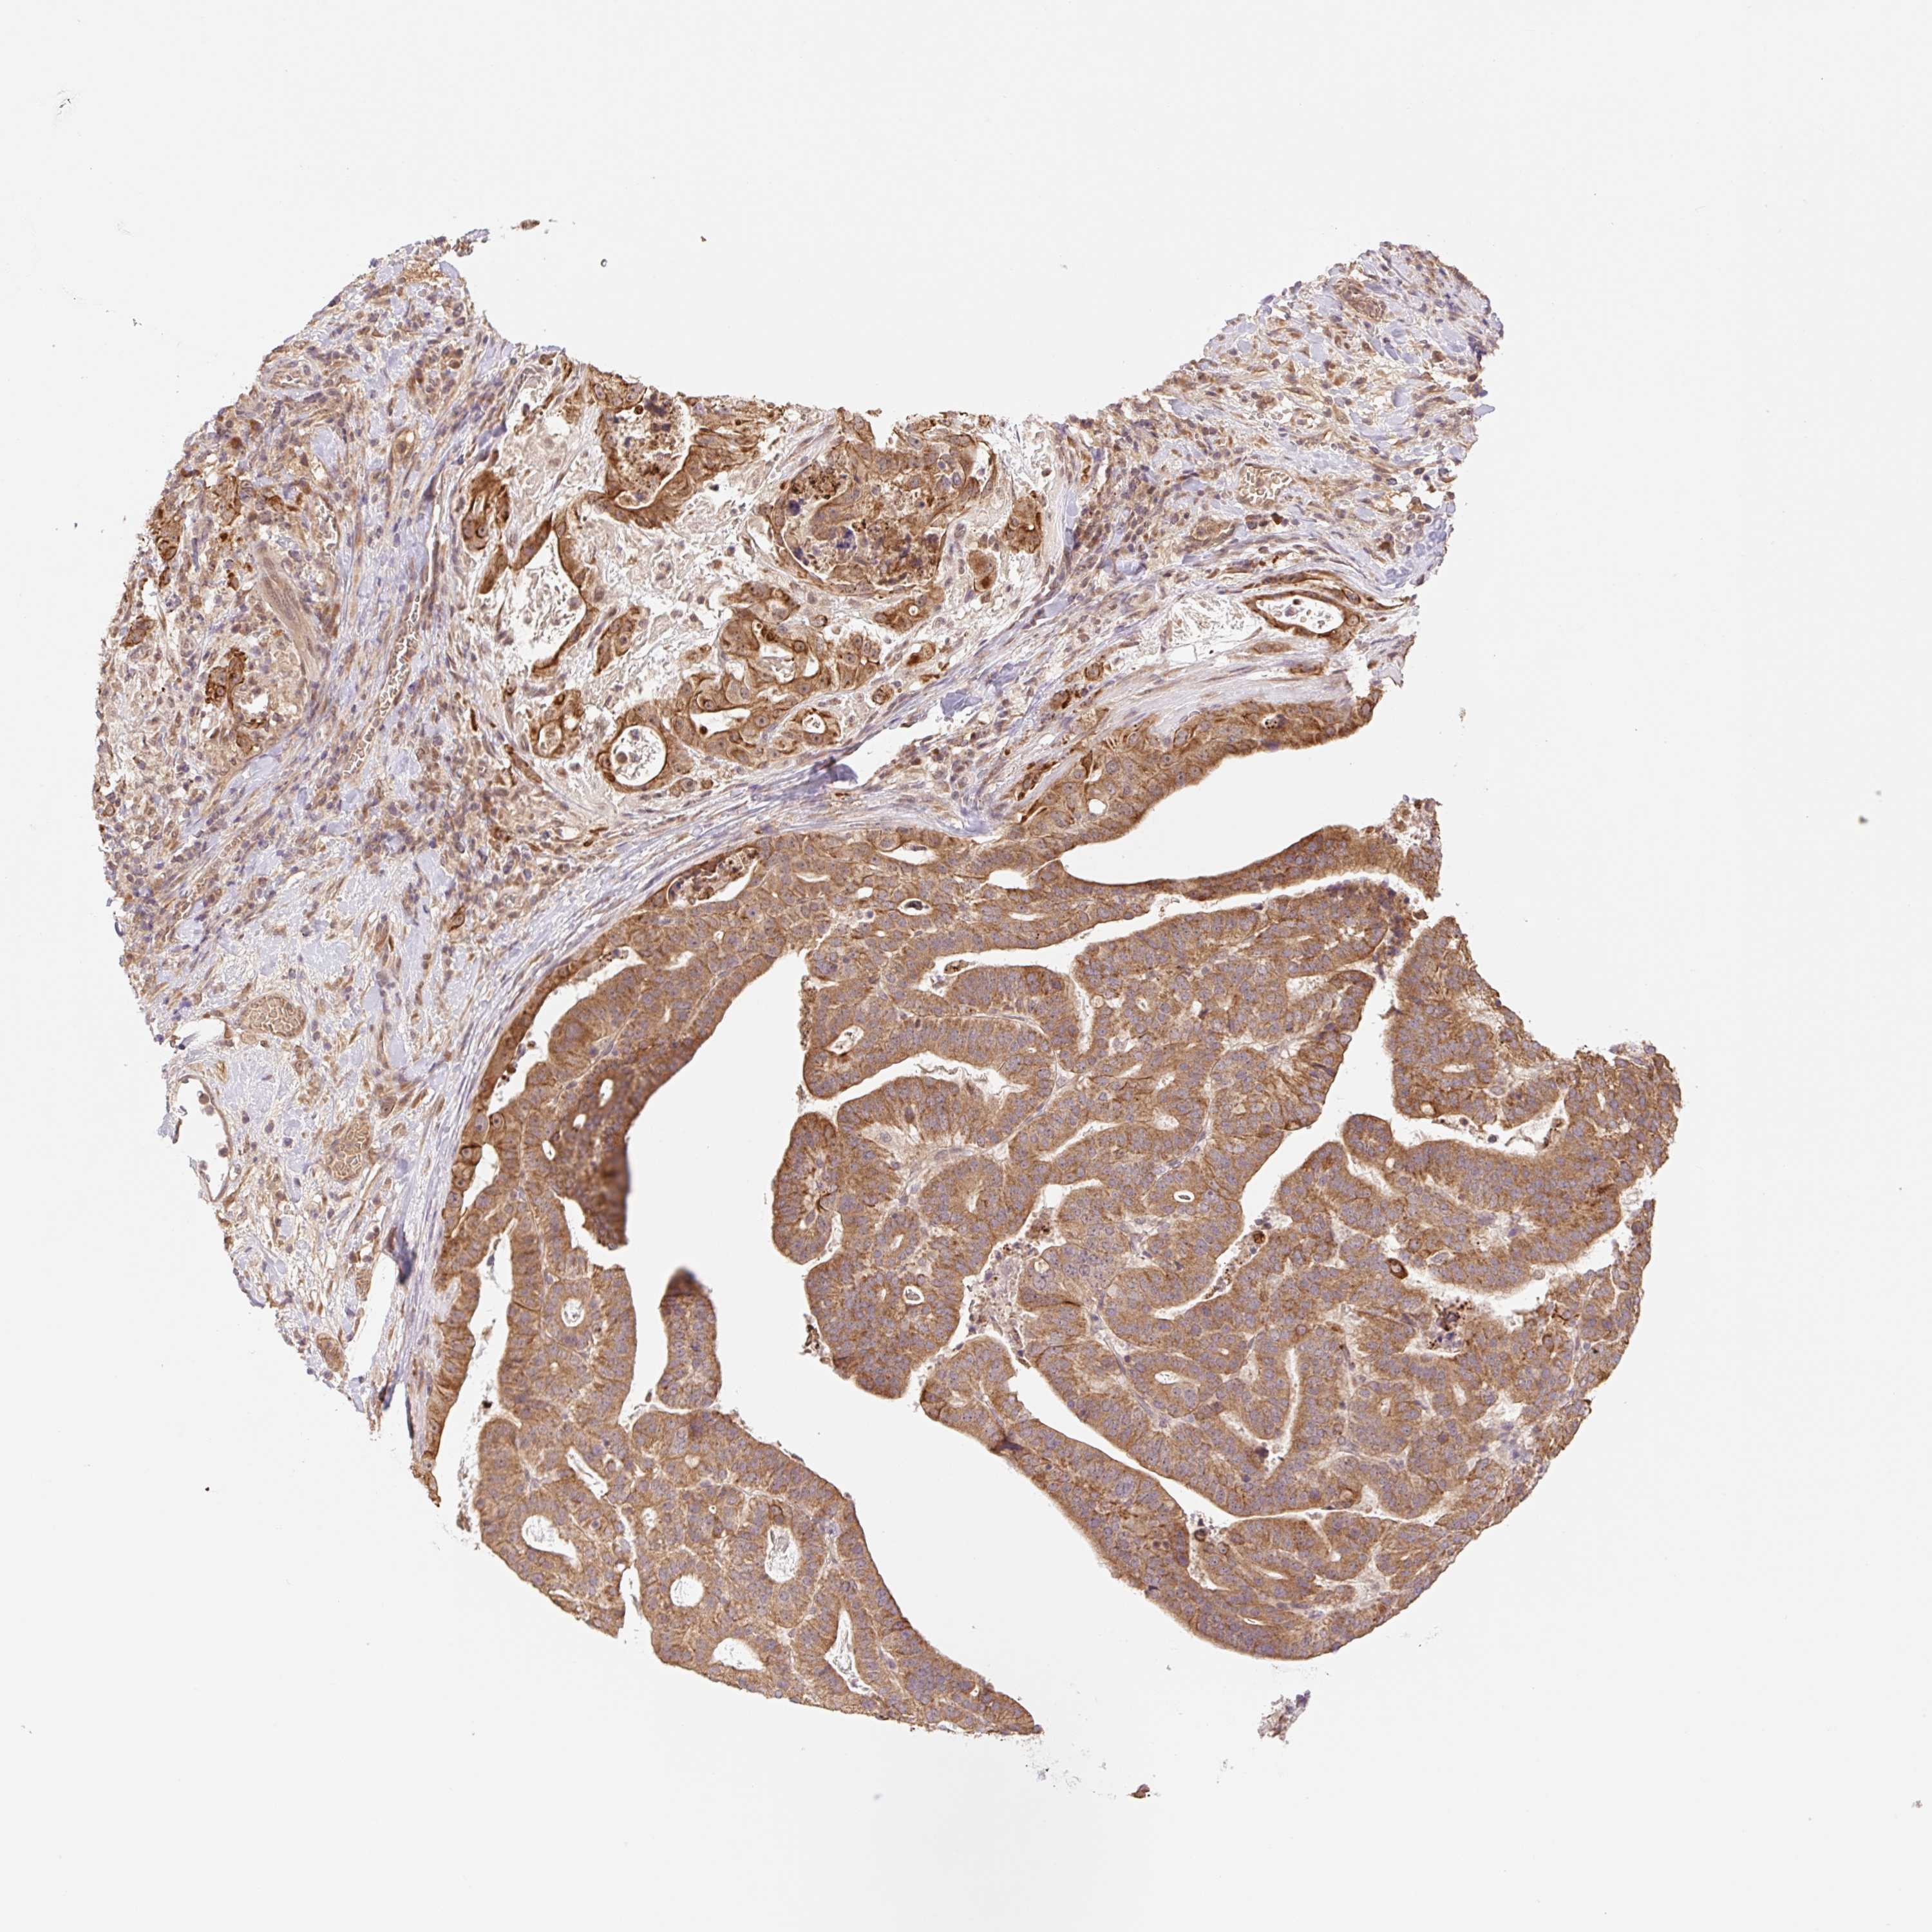

STOMACH CANCER - Protein expressioni

A mouse-over function shows sample information and annotation data. Click on an image to view it in a full screen mode. Samples can be filtered based on level of antibody staining by selecting one or several of the following categories: high, medium, low and not detected. The assay and annotation is described here.

Note that samples used for immunohistochemistry by the Human Protein Atlas do not correspond to samples in the TCGA dataset.

Antibody stainingi

Antibody staining in the annotated cell types in the current human tissue is reported as not detected, low, medium, or high, based on conventional immunohistochemistry profiling in selected tissues. This score is based on the combination of the staining intensity and fraction of stained cells.

Each image is clickable and will lead to virtual microscopy that enables deeper exploration of all samples and also displays staining intensity scores, fraction scores and subcellular localization as well as patient and tissue information for each sample.

Antibody HPA056977

Staining

High

Medium

Low

Not detected

Intensity

Strong

Moderate

Weak

Negative

Quantity

>75%

75%-25%

<25%

None

Location

Nuclear

Cytoplasmic/membranous

Cytoplasmic/membranous,nuclear

Adenocarcinoma, NOS